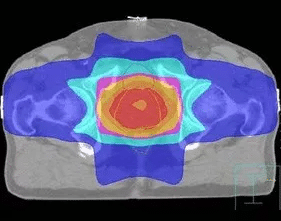

利用多葉光柵或適形擋鉛技術(shù),將照射野的形狀由普通放療的方形或矩形調(diào)整為腫瘤的形狀,從而使照射的高劑量區(qū)在人體內(nèi)的三維立體空間上與腫瘤的實(shí)際形狀相一致。三維適形放療提高了腫瘤的照射劑量,保護(hù)了腫瘤周圍的正常組織,降低了放射性并發(fā)癥,提高腫瘤的控制率。

與常規(guī)放療相比,3DCRT對腫瘤組織的適形聚焦照射和對正常組織的良好保護(hù),提高了腫瘤與正常組織的計(jì)量比。在正常組織受到允許劑量照射的情況下,腫瘤組織可以得到比常規(guī)放療更高的總劑量。治療時(shí)可以明顯地提高單次劑量,縮短總的治療時(shí)間??梢愿行У乇Wo(hù)正常組織,降低放射損傷,提高腫瘤的局部控制率。

適形放療是根據(jù)腫瘤的立體大小,從三維方向上,采用多野、多角度進(jìn)行照射,而且每個(gè)照射野的截面形狀與對應(yīng)的腫瘤形狀相一致。靶區(qū)形狀雖已適形,但靶區(qū)內(nèi)劑量分布欠均勻。